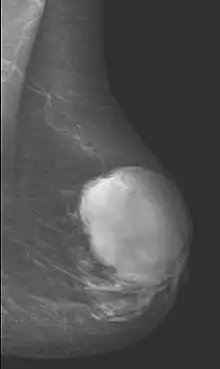

Radiographical imaging is the first-line test for identifying a phyllodes tumor.[11] Despite their propensity to grow rapidly and deform the overlying breast tissue, approximately 20% of phyllodes tumors can present as a nonpalpable mass on screening mammography.[12] Other imaging tools used to assess the size and spread of a phyllodes tumor include ultrasound and magnetic resonance imaging (MRI).[11] None of these imaging tools are definitive tests for differentiating a phyllodes tumor from a benign fibroadenoma.[13] Phyllodes tumors can only be diagnosed histologically, as they tend to have many overlapping features with other breast masses on physical examination and radiological imaging.[11]